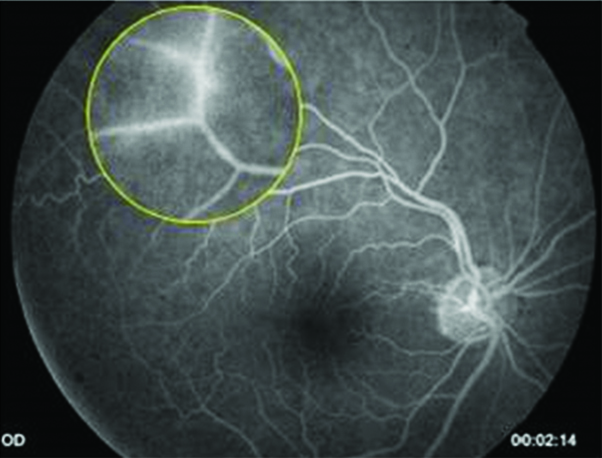

Fue derivada a oftalmología por presentar dificultad en la visión, descripta como ¨falta de visión periférica¨, alteración compatible con escotoma temporal superior en ambos ojos (AO). Al examen de fondo de ojos se observan vasos exangües, arrosariamiento venoso y vasculitis temporal inferior en AO (Imágenes 3, 4, 5 y 6). Se realiza campo visual sólo de ojo derecho (Imagen 7), por incapacidad de la paciente para completar el examen del ojo izquierdo debido a la dificultad motora que presenta. Se puede observar un escotoma relativo superior. En la retinofluoresceinografía (RFG) se localiza un área de hiperfluorescencia perivascular, en tiempos medios compatible con vasculitis periférica de AO (Imágenes 8 y 9) y con la alteración visual descripta por la paciente.

Imágenes 8 y 9:

RFG OD y OI respectivamente, donde se puede localizar la alteración en la permeabilidad vascular inferotemporal de la retina, vasculitis, compatible con la imagen que refiere la paciente en AO. Placas de Gass: segmentos arteriolares ocluidos junto con otros, vasos fantasmas o rayos de plata, a menudo localizados en bifurcaciones.